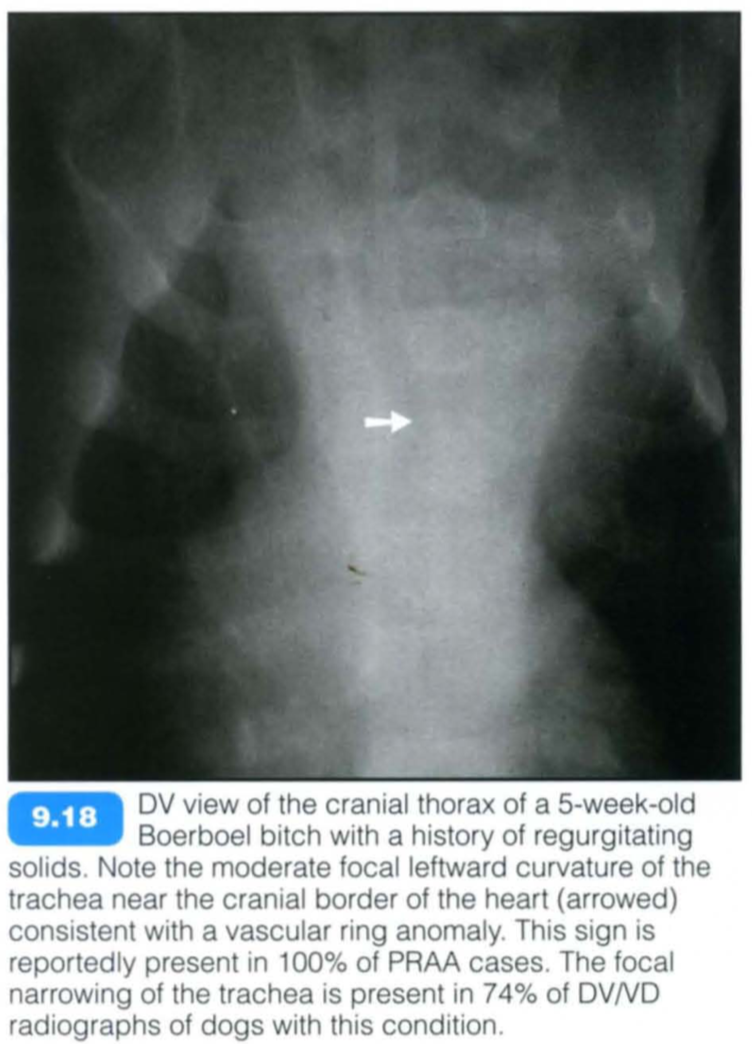

Vascular ring anomalies are congenital malformations of the major arteries of the heart that entrap the intrathoracic oesophagus and cause oesophageal obstruction. The condition is likely to be heritable in German Shepherd Dogs, Irish Setters and Greyhounds. Vascular ring anomalies are uncommon in the cat.

Certain clinical signs are similar in all vascular ring anomalies. Most animals present as thin and stunted with a history of regurgitation of solid foods at the time of weaning. Rarely, the ductus arteriosus may remain patent in PRAA (corresponding radiographic signs of patent ductus arteriosus (PDA) should be looked for) and can be auscultated with its characteristic machinery or continuou s murmur. Patients with double aortic arch anomalies may be dyspnoeic due to concomitant entrapment of the trachea.

The prognosis is variable as the oesophageal dilatation and hypomotility are not fully reversible. In general, patients with generalized megaoesophagus or dilatation caudal to the heart have a poor prognosis, and contrast medium administration may be necessary to evaluate this. The earlier the condition is corrected, the better the prognosis.

Radiographic findings include:

Contrast studies: